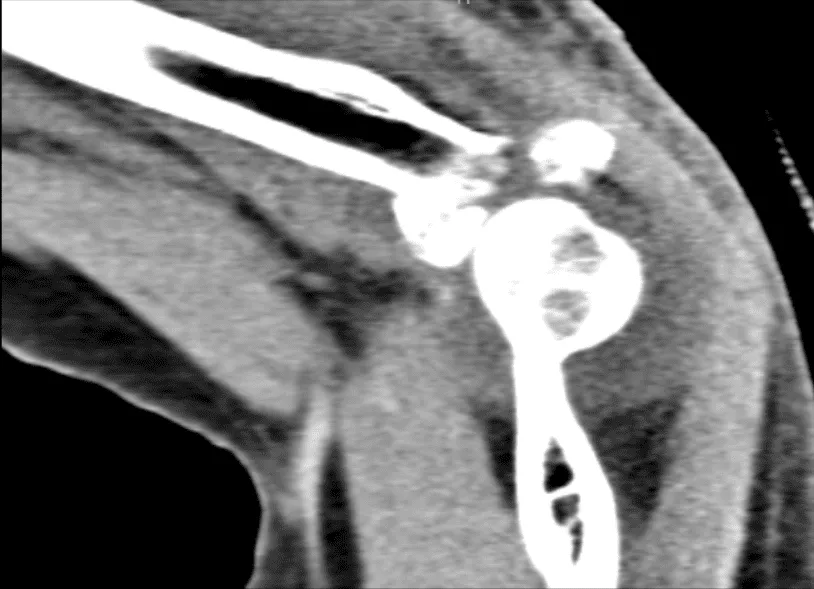

El paciente presentó un resultado de tomografía computarizada que mostró fractura aguda conminuente desplazada de la cabeza radial como se describió anteriormente. Esencialmente fractura aguda no desplazada del proceso coronoides del cúbito. Hemartrosis.

TC codo izquierdo sin contraste